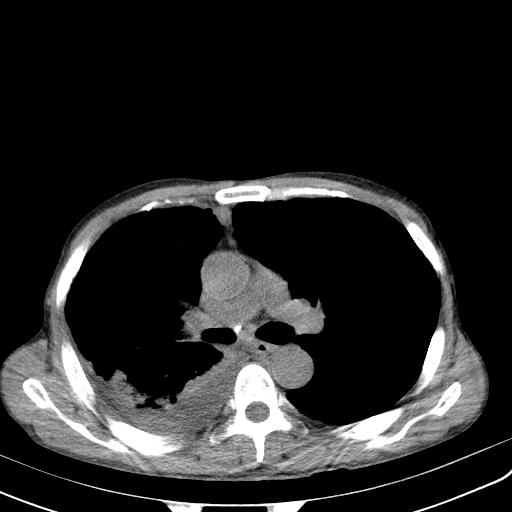

男性 75  咳嗽 一周前发热最高达39

右肺继发型tb并右侧tb性胸腔炎,右侧胸腔大量积液并右下肺膨胀不全,慢支肺气肿、多发肺大泡。建议抽胸水实验室检查并复查排除恶性在占位。

右上肺继发型肺结核,右胸腔中等量积液。

左上肺大泡。

结核的基础上有纵隔淋巴结肿大,右侧有胸水,但右侧纵隔反而窄,说明有肺有不张。

再就是右下肺有块影,和不张混合,还是不能除外肺癌。

1)右肺继发型肺结核。2)左肺胸膜下多发性肺大泡。3)右侧胸腔积液。